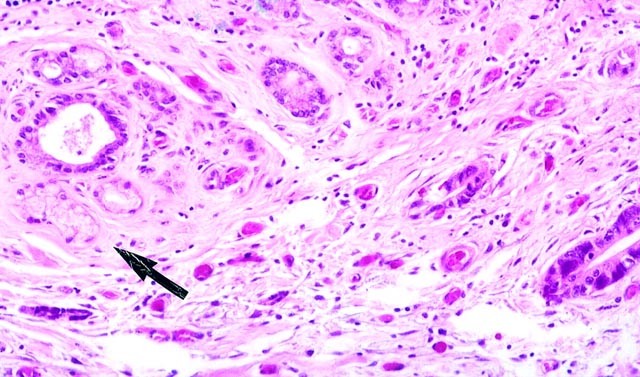

Neoplastic glands are present adjacent to the metaplastic glands (arrow).

FIGURE 8